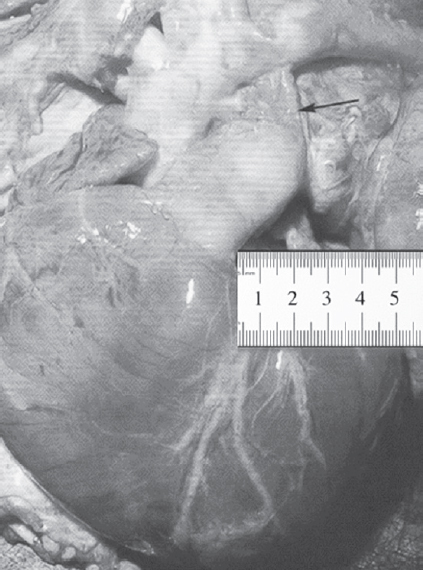

В норме ОАП обязательно закрывается вскоре после рождения, превращаясь в ligamentum arteriosum [14, 16]. Если же проток не закрывается или происходит его частичная облитерация, говорят о наличии порока [2, 5, 9, 19]. ОАП — «несовершенный» порок сердца, или «условный» врожденный порок, так как говорят о нем как о пороке только лишь после рождения (рис. 16). ВПС ОАП считается изолированным при условии, что проток служит единственным местом шунтирования крови из одного круга кровообращения в другой, из большого в малый, в то время как все другие отделы сердца сформированы правильно [4].

Рис. 16. Препарат сердца плода. Указателем обозначен артериальный проток шириной 1,2 см, длиной 2,6 см

Fig. 16. Fetal heart preparation. The pointer indicates an arterial duct with a width of 1.2 cm, a length of 2.6 cm